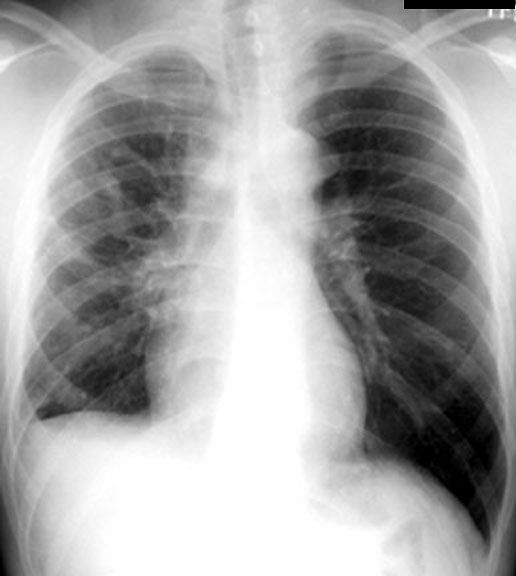

Pleural Fibrosis

• Small right hemithorax

• Diffuse haziness

• Blunted costophrenic angle